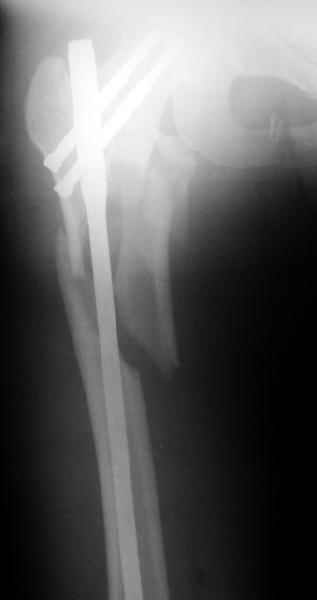

Другое наблюдение:Мужчина, 1957 г.р. Травма в результате ДТП 12.09.04г.

Диагноз: Закрытый оскольчатый подвертельный перелом правой бедренной кости со смещением отломков, оскольчатый перелом большого вертела, отрывной перелом малого вертела.Сопутствующие заболевания: Язвенная болезнь желудка, ремиссия.

Наверно, можно и так сказать, но можно и тоже самое - 4-фрагментный вертельный перелом. Выбор тот же, но с учетом молодого возраста реконструкционный гвоздь тут более применим. Вот уже наш пример.

Перелом подвертельный. Лечение оперативное, срочное,

PFN с длинной ножкой чтобы избежать стрессовые изменения в будущем. Обычно у молодых людей требуется проводить рассверливание канала как при гвоздевании.